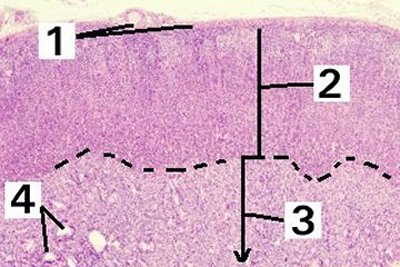

This is a very low magnification of the adrenal gland demonstrating the capsule and layers.

Fig 56-001 1. Capsule

2. Cortex

3. Medulla

4. Blood vessels